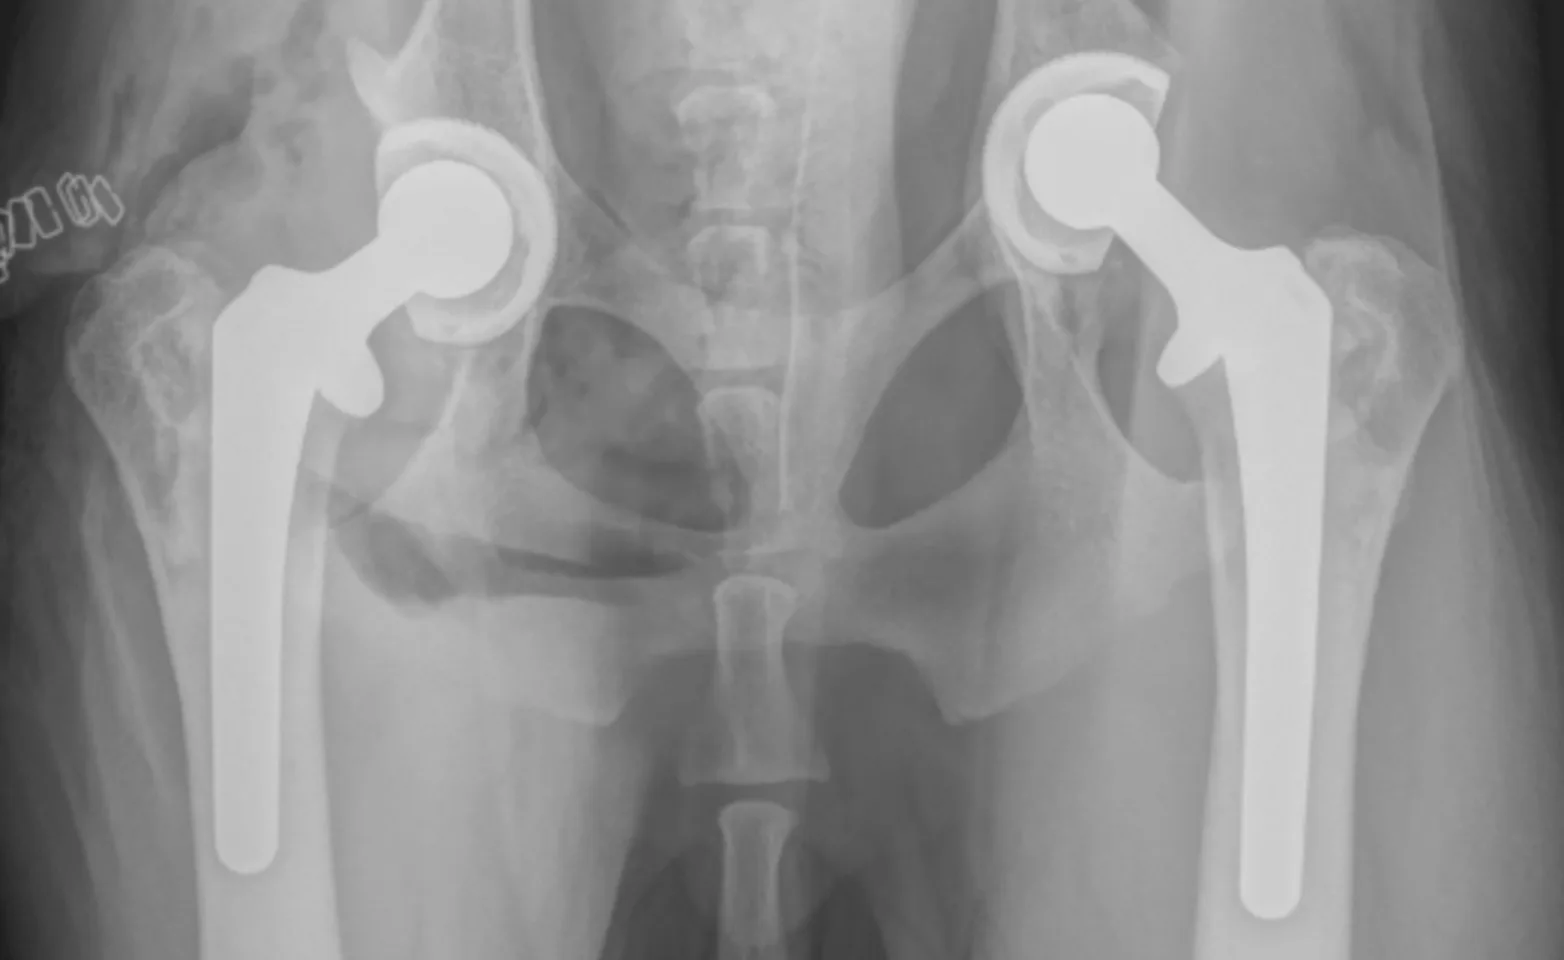

Total hip replacement (THR)